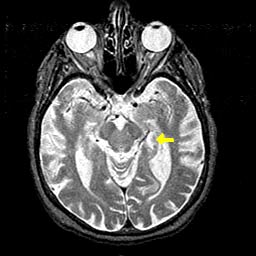

The amygdala is a structure located deep in the anterior inferior temporal lobe of the brain. The amygdala receives projections mostly from the sensory regions of the thalamus and the cortex, but also from several other structures such as the hippocampus and the prefrontal cortex.

Another important pathway emerging from the amygdala is the stria terminalis, which is to the amygdala as the fornix is to the hippocampus. Like the fornix, the stria terminalis projects only to sub-cortical structures such as the hypothalamus and the septum. The hypothalamus and the septum also receive projections from the amygdala by another route–the ventral amygdalofugal pathway–as well as from the hippocampus. Moreover, the hippocampus and the amygdala are located beside and have many connections with each other.

The hippocampus is the structure that supports the explicit memory required to learn about the dangerousness of an object or situation in the first place. The hippocampus is also especially sensitive to the encoding of the context associated with an aversive experience. It is because of the hippocampus that not only can a stimulus become a source of conditioned fear, but so can all the objects surrounding it and the situation or location in which it occurs.